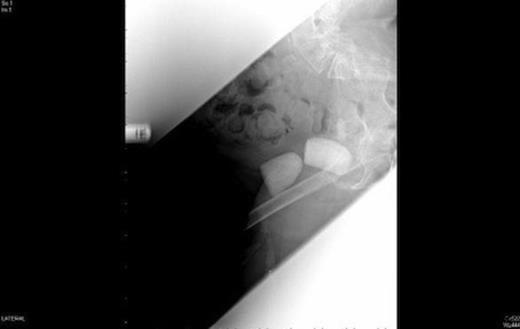

A urology opinion was sought, initially, with regard to management of the suprapubic catheter. On closer examination, urine was noted to be leaking not from the suprapubic site but around the calcified mass in the right groin and a diagnosis of vesicocutaneous fistula was made. Her radiographs demonstrated two urinary calculi (Fig 1) and she went on to have an abdominal computed topography scan (Fig 2 ) which confirmed the diagnosis of a vesicocutaneous fistula.

CT demonstrating the two bladder calculi pointing towards the right groin